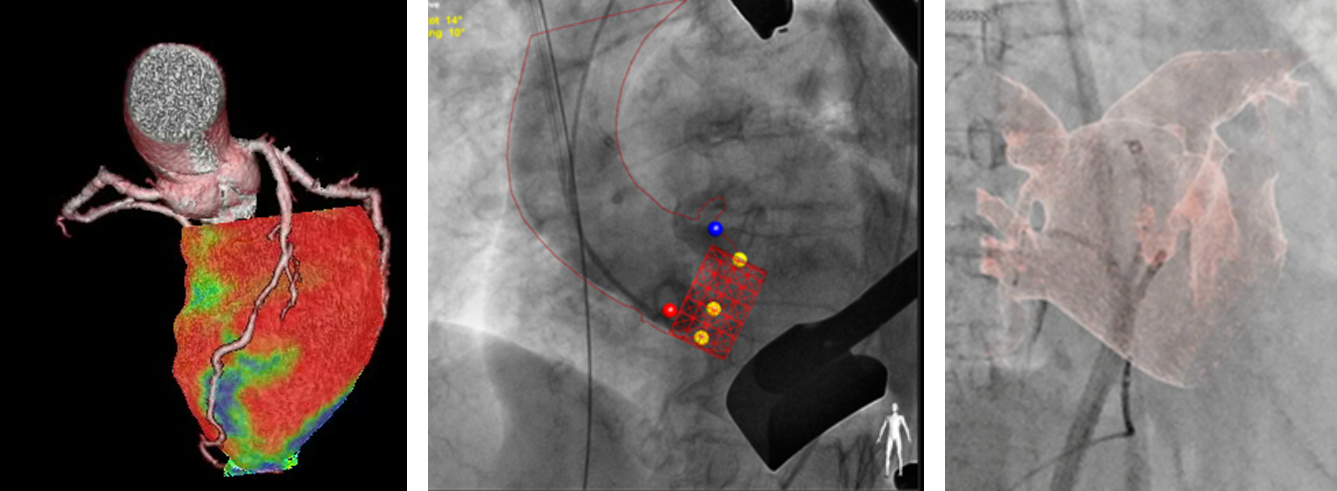

심장혈관질환 융합 이미징(Coronary artery tree and ischemic myocardial territory, planning of TAVI, CT as roadmap for live fluoroscopic image)

그림 2. 심장혈관질환 융합 이미징

(Coronary artery tree and ischemic myocardial territory, planning of TAVI, CT as roadmap for live fluoroscopic image)

CT 는 공간적 및 시간적 해상도가 제한되어 있어 모든 관상동맥을 정확히 평가하기는 어렵다. 그러나 구조적 심장질환 (structural heart disease) 과 판막질환 및 대동맥과 말초혈관질환에서는 관상동맥보다 해상도의 제한이 적어 장점이 많다. CT 이미징 결과를 바탕으로 디바이스의 크기와 종류 및 시술에 가장 적합한 투시각도를 결정할 수 있고 투시에서 보이는 영상을 보다 잘 이해할 수 있다. 자기공명영상 (magnetic resonance imaging, MRI) 는 시간적 해상도가 CT 보다 우수하고 혈관 외 심근과 같은 연부조직을 잘 볼 수 있으며 이온화 방사선의 노출이 없다는 큰 장점이 있다. 현재는 CT 나 MRI 를 시술 전 독립적으로 시행하고 이를 오프라인 영상으로 시술 중 활용하고 있으나, 수술과 투시를 사용하는 시술을 겸하는 하이브리드 수술방에 추가로 CT 나 MRI 장비를 설치하여 시술 중 실시간 영상을 얻어 시술에 활용하는 전략이 연구되고 있으며 시술과정의 보조에 큰 도움이 될 것으로 보인다. MRI 는 특히 시술 시간이 긴 전기생리학적 치료에 방사선노출을 낮추는데 유용할 것으로 기대되고 있다.14-18